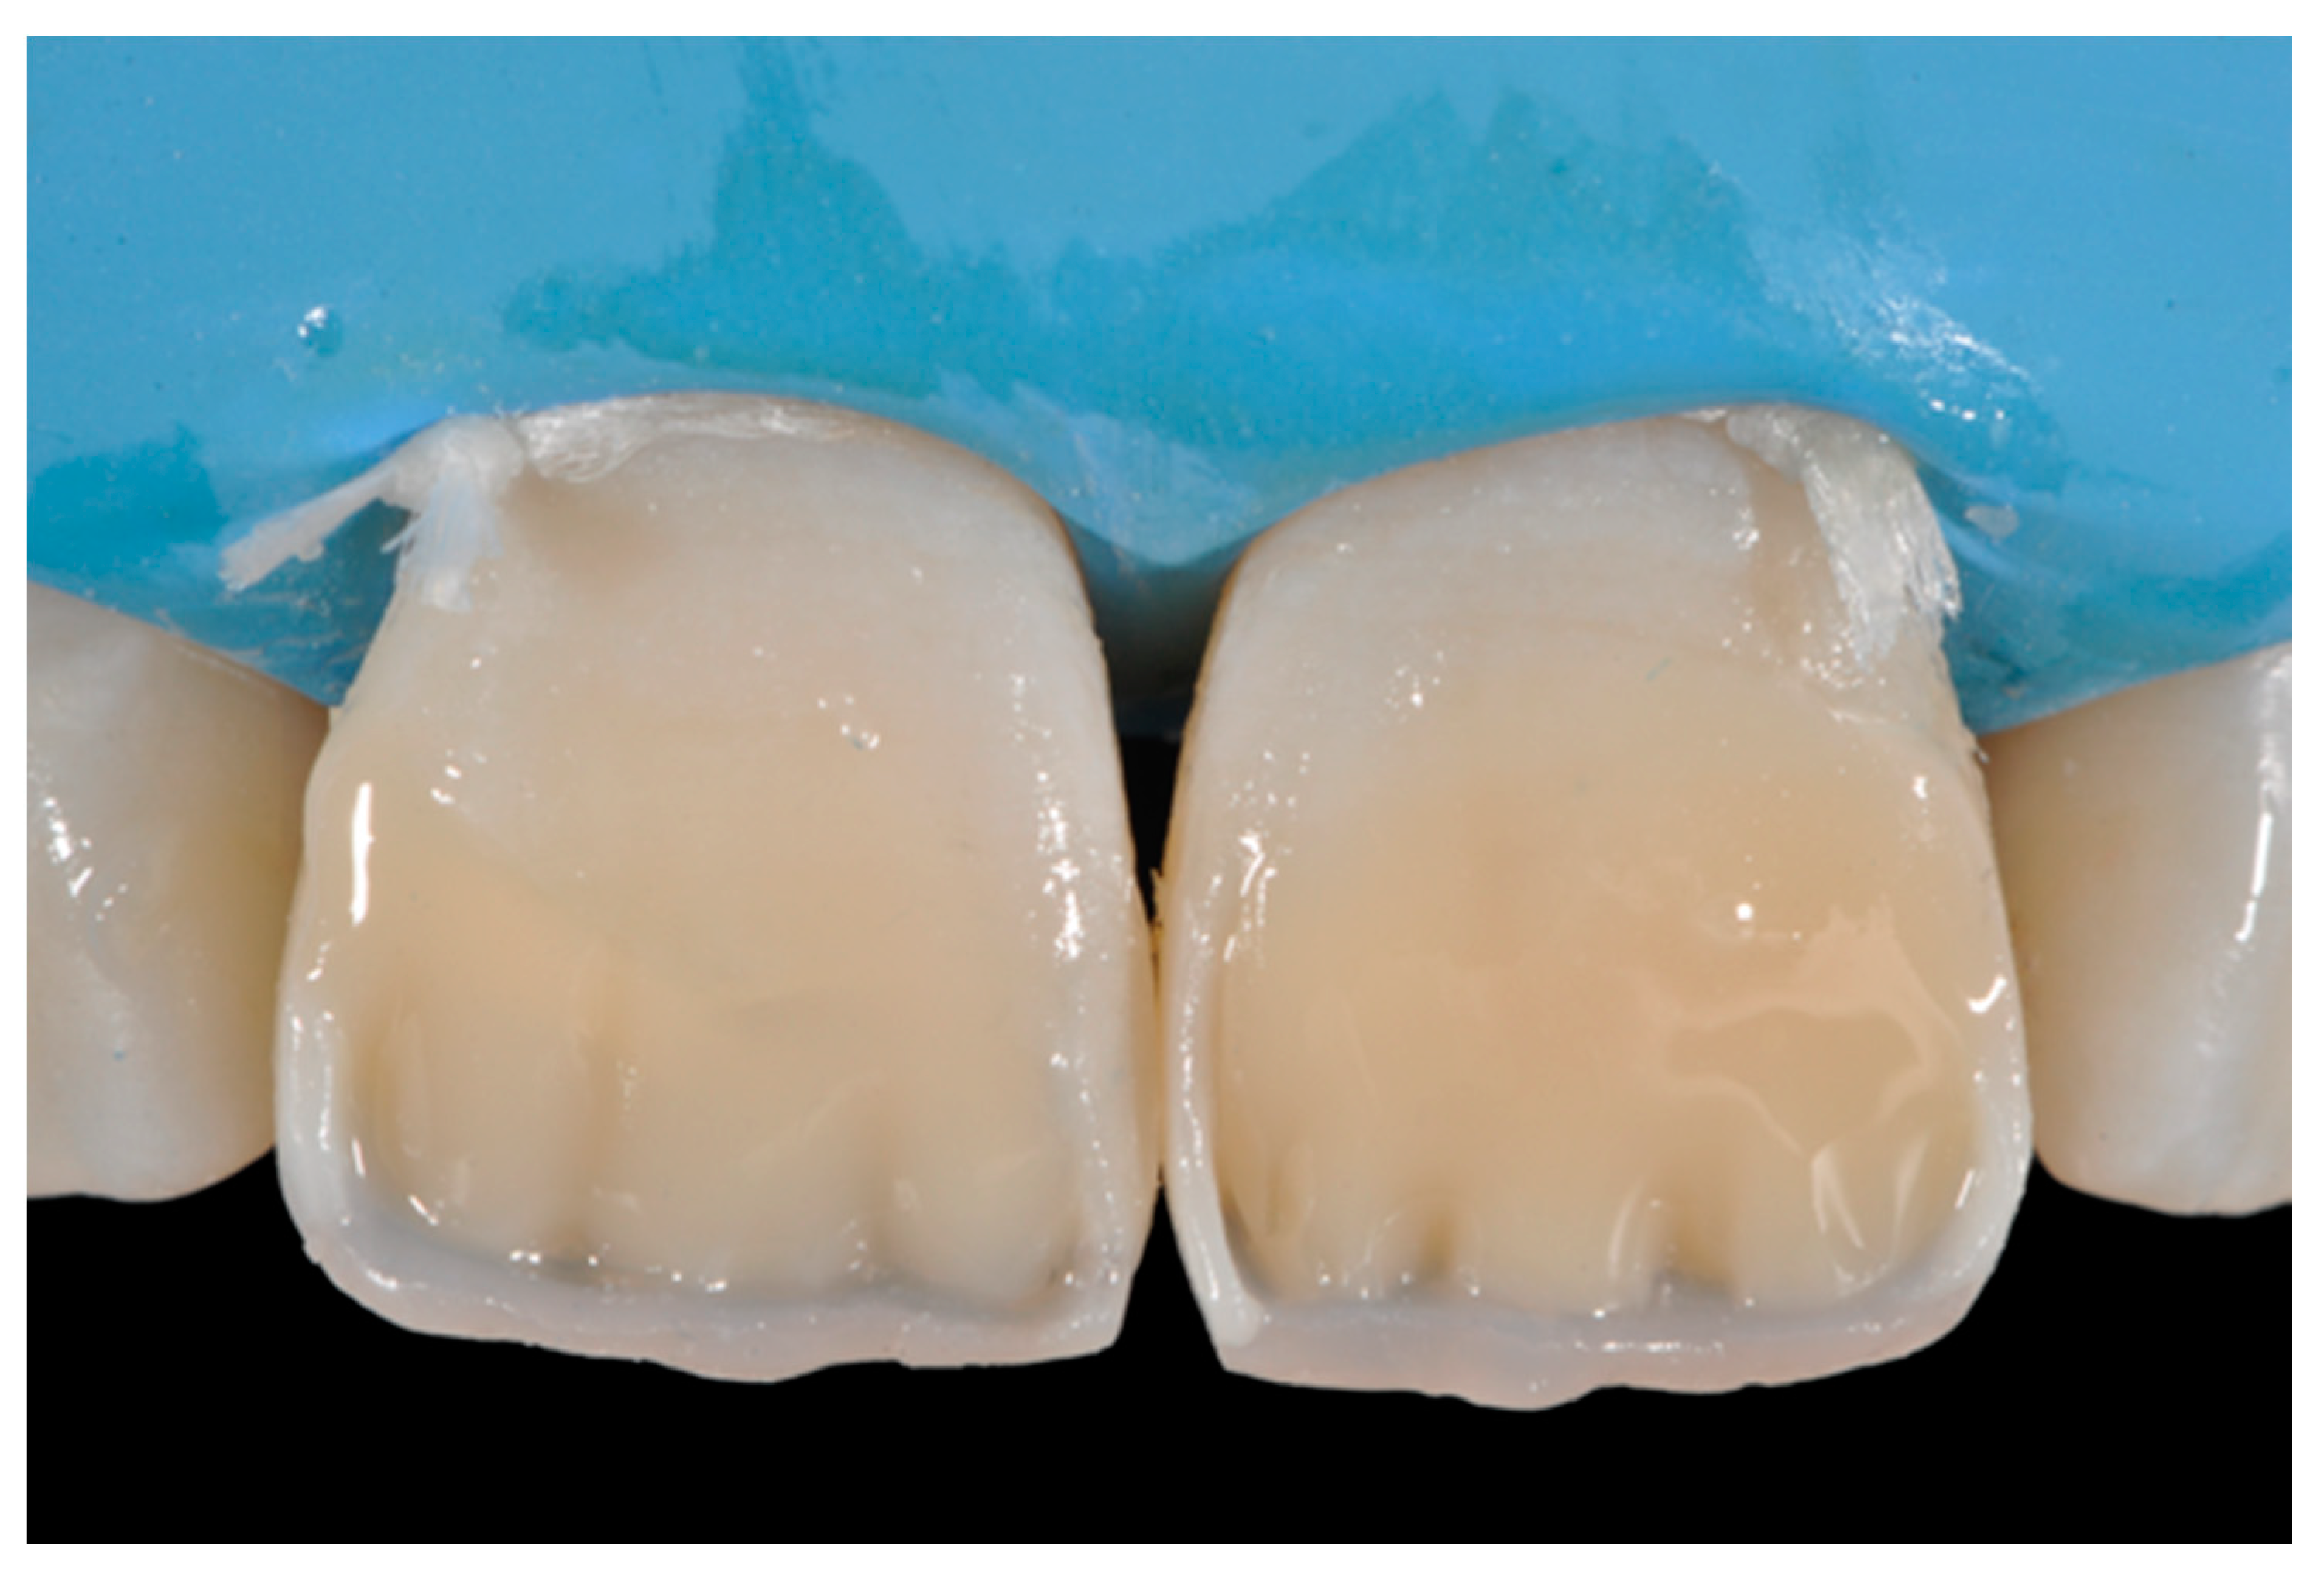

Once completed, the two frames (Clearfil Majesty ES-2, A1E, A2D, Kuraray Noritake Dental, Tokyo, Japan) showed internal and external excesses that were reduced using diamond burs and discs (Figure 33 and Figure 34) strictly following the procedure described in Section 2.1.2 of present article. Excesses were removed from the distal-incisal angle of #2.1 allowing therefore to obtain the desired translucency. After silane application and bonding procedure (Figure 35) as described in Section 2.1.2, restorations were completed (Figure 36 and Figure 37). They both show satisfactory clinical integration 1.5 years post-operative (Figure 38 and Figure 39).

Figure 35.

The modified frames treated with silane coupling agent and adhesive, ready for layering of dentinal body. Reprinted from Restauri diretti nei settori anteriori, G. Paolone, S. Scolavino, © 2021, with permission from Quintessence Publishing Italy.